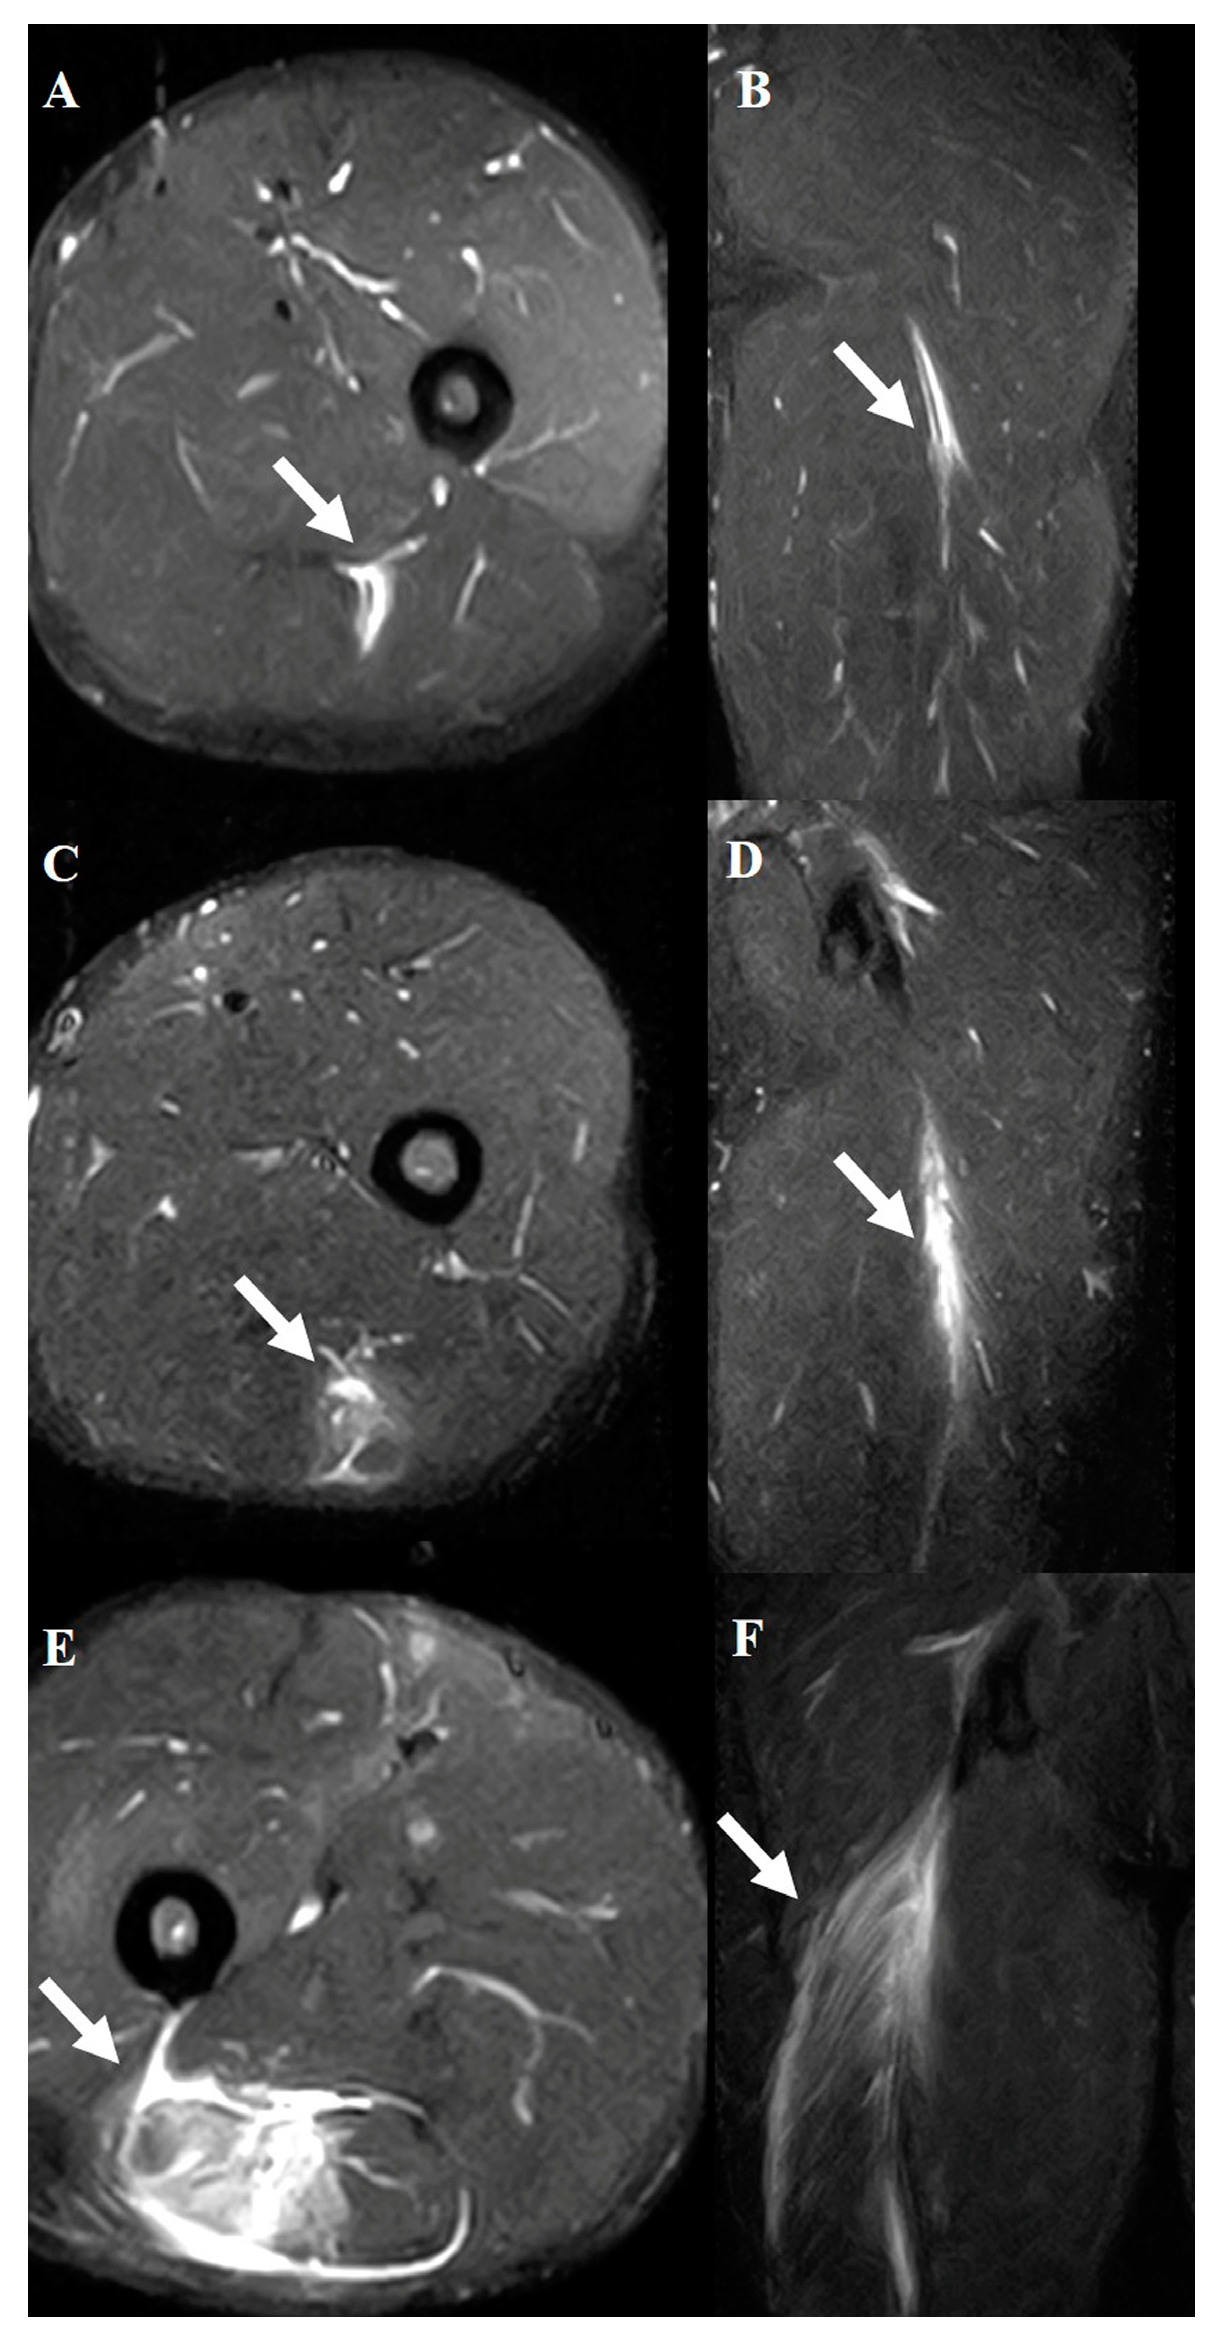

2.4. Hamstring Muscle Diagnosis Using MRI